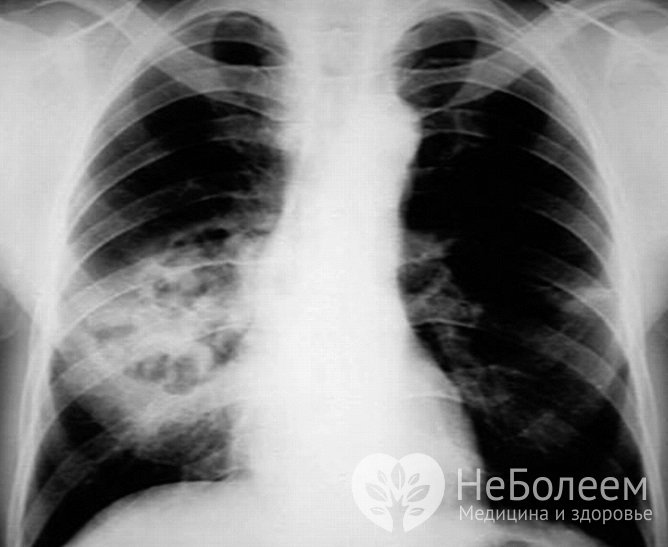

• рентген легких. Снимок дает возможность определить очаг воспаления, его размер и наличие осложнений.